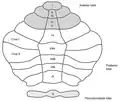

The vermis is the unpaired, median portion of the cerebellum that connects the two hemispheres.[9] Both the vermis and the hemispheres are composed of lobules formed by groups of folia. There are nine lobules of the vermis: lingula, central lobule, culmen, clivus, folium of the vermis, tuber, pyramid, uvula and nodule.[9] These lobules are often difficult to observe during human anatomy classes and may vary in size, shape and number of folia. It has been shown that folia of the cerebellum exhibit frequent variations in form, number and arrangement between individuals.[9]

The lingula is the first lobule of the upper portion of the vermis on the superoinferior axis and pertains to the paleocerebellum together with the central lobule, culmen, pyramid and uvula. It is separated from the central lobule by the pre-central fissure. The central lobule is the second lobule of the upper portion of the vermis on the superoinferior axis. The culmen is the third and largest lobule of the upper portion of the vermis on the superoinferior axis. It is separated from the declive by the primary fissure and is related with the anterior quadrangular lobule of the hemisphere. The pyramid is the seventh lobule of the vermis on the superoinferior axis. It is separated from the tuber and uvula by the pre-pyramidal and secondary fissures, respectively.[9] This lobule is related with the biventral lobule of the hemisphere. The uvula is the second largest lobule, following the culmen. It pertains to the paleocerebellum and is separated from the nodule by the posterolateral fissure.[9]

Lobules of the vermis.

Lobules of the vermis.